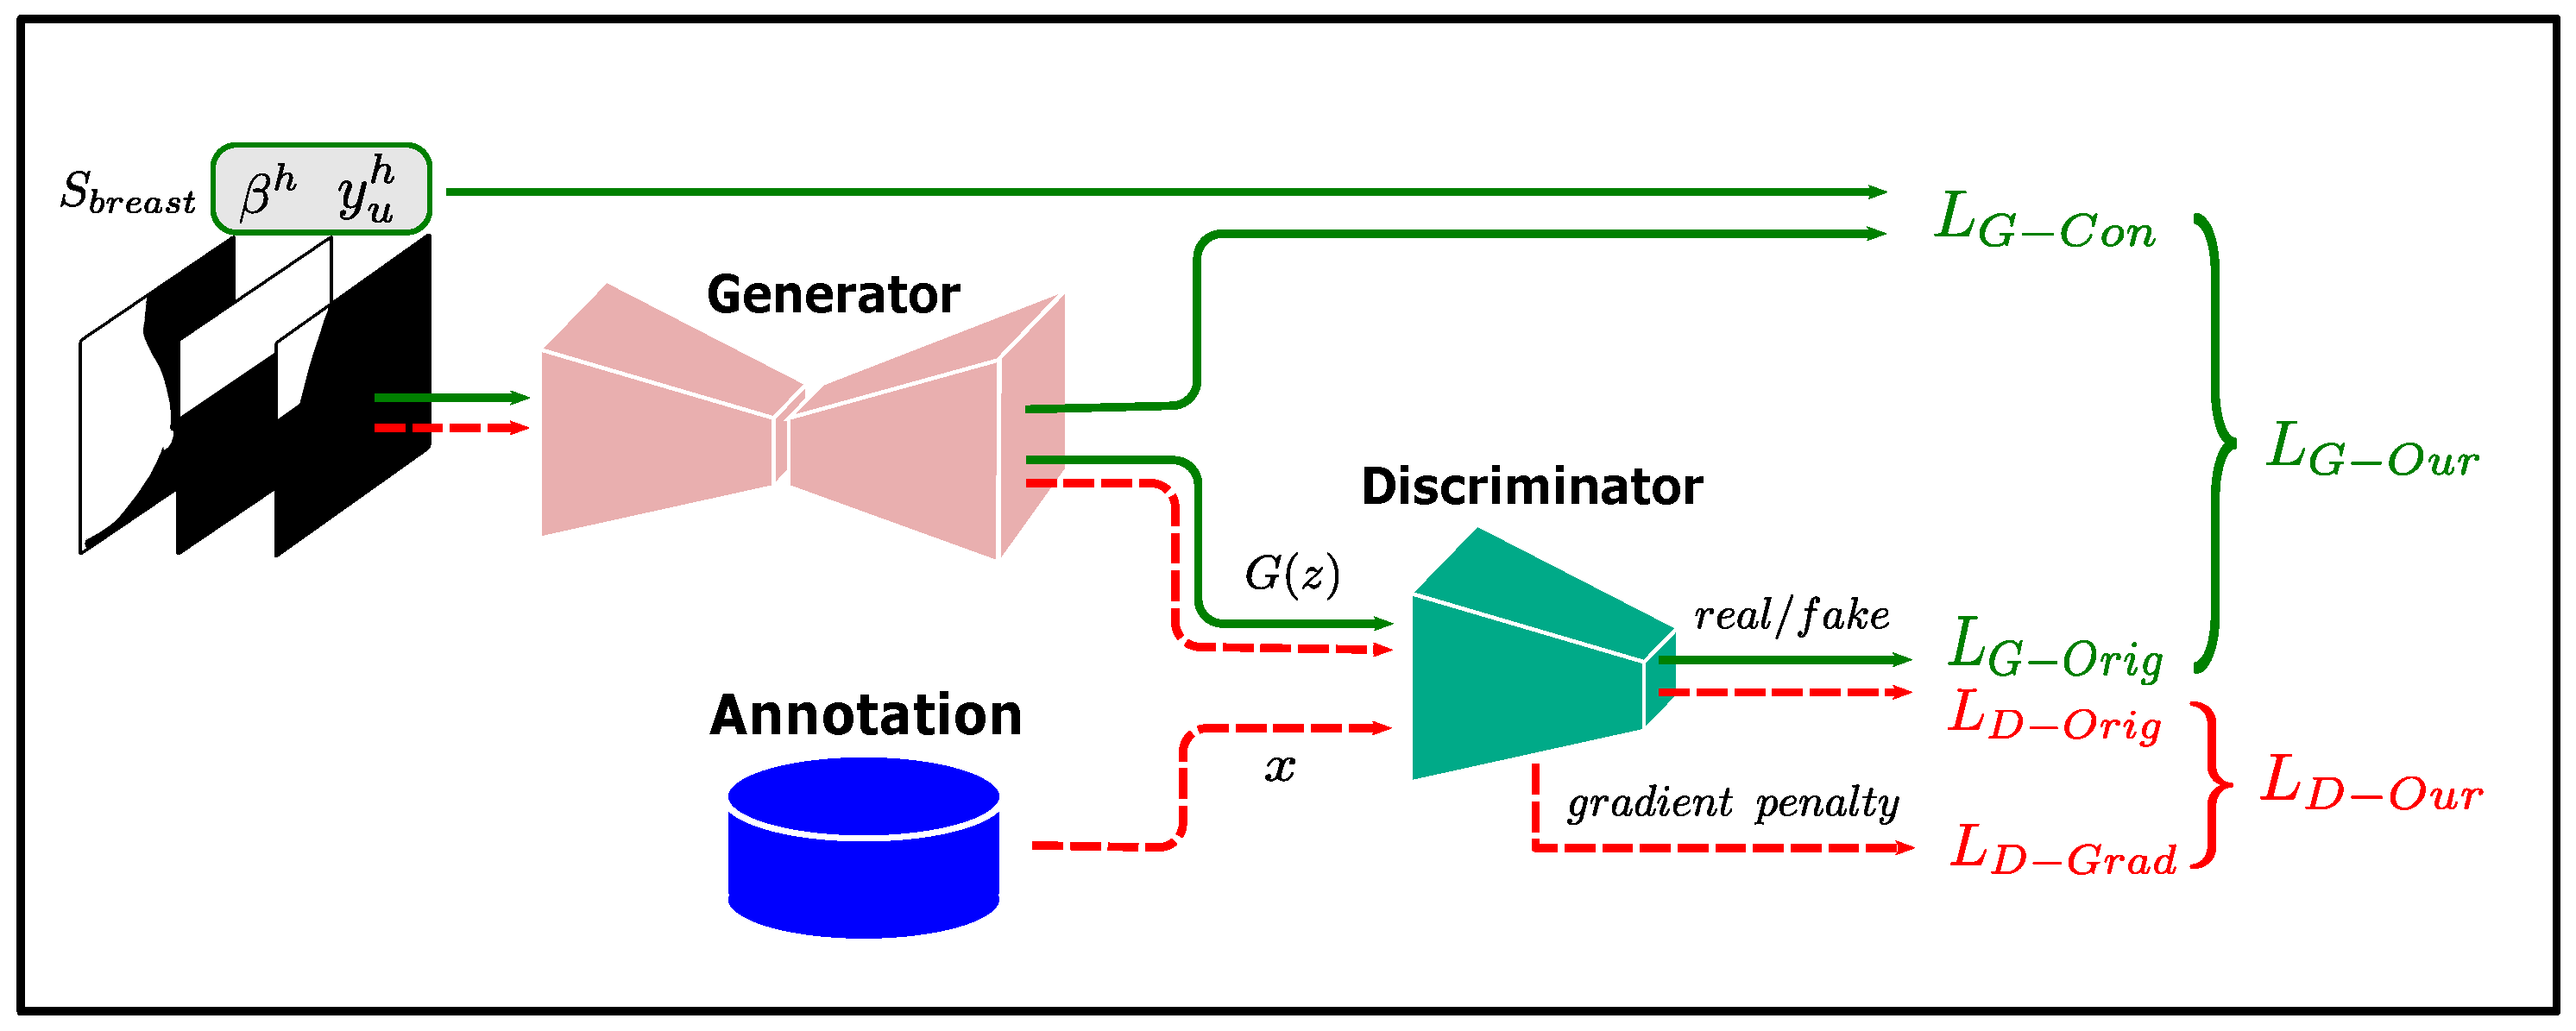

2.4. Low-Confidence Prediction Refinement

- Leveraging domain-related information contained in the low-confidence prediction region. Recent studies on domain adaptation [42,43] show that models tend to produce low-confidence predictions when the target and source data domains differ. This suggests that low-confidence predictions may be caused by the presence of domain-related information in the target data domain that has not been learned by the model. Directly constructing consistency regularization terms using these low-confidence predictions can cause the model to suffer from confirmation bias. Meanwhile, using the strategy of discarding low-confidence predictions, as in recent studies, loses the opportunity to fully learn the domain-relevant information from the dataset. We draw on the experience of doctors when performing delineation and refine the low-confidence predictions using high-confidence predictions as well as the learned prior to enable the model to fully learn the domain-relevant information from the dataset. In the experiments, our method outperformed the other two methods in all evaluation metrics.

- The utilization of prior knowledge reduces the dependence of target predictions on the teacher predictions and improves the accuracy and stability of model training. The GAN used in the low-confidence predictions refinement module learns the anatomical prior of the breast and pectoral muscle in mammograms, which provides regularization constraints for the target predictions used in the student model training. Therefore, fluctuations in the performance of the teacher model will not have a large impact on the target predictions. Moreover, GAN uses domain-independent semantic features as input, and its main reliance on the teacher model is the high-confidence predictions, which are usually easy to learn. Thus, the low-confidence prediction refinement module can provide regularization constraints for target predictions that do not vary by the data center.